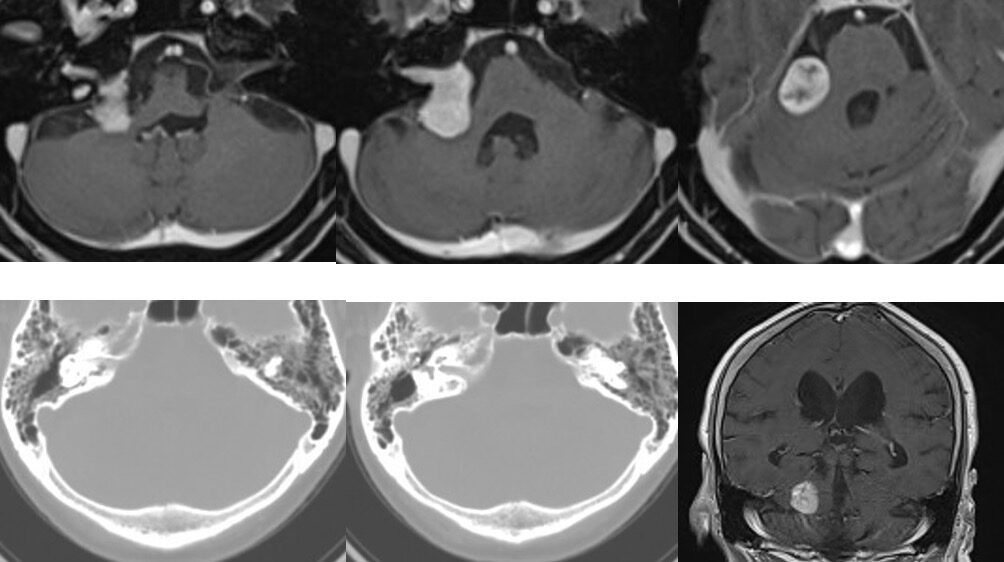

手術は通常通り行われ、顔面神経の麻痺を起こさずに摘出は終了し、うまくいったと考えていました。しかし術後より覚醒障害が続き、強い小脳腫脹を生じたため、術後脳室ドレナージ術、バルビタール麻酔療法、気管切開まで行い急性期を乗り切りました。術前より下肢静脈血栓症を合併していたことと、Petrosal veinが通常より広範囲の静脈環流を行っていたためと考えられます。現在、覚醒し、四肢が動くようになってきました。

手術は通常通り行われ、顔面神経の麻痺を起こさずに摘出は終了し、うまくいったと考えていました。しかし術後より覚醒障害が続き、強い小脳腫脹を生じたため、術後脳室ドレナージ術、バルビタール麻酔療法、気管切開まで行い急性期を乗り切りました。術前より下肢静脈血栓症を合併していたことと、Petrosal veinが通常より広範囲の静脈環流を行っていたためと考えられます。現在、覚醒し、四肢が動くようになってきました。